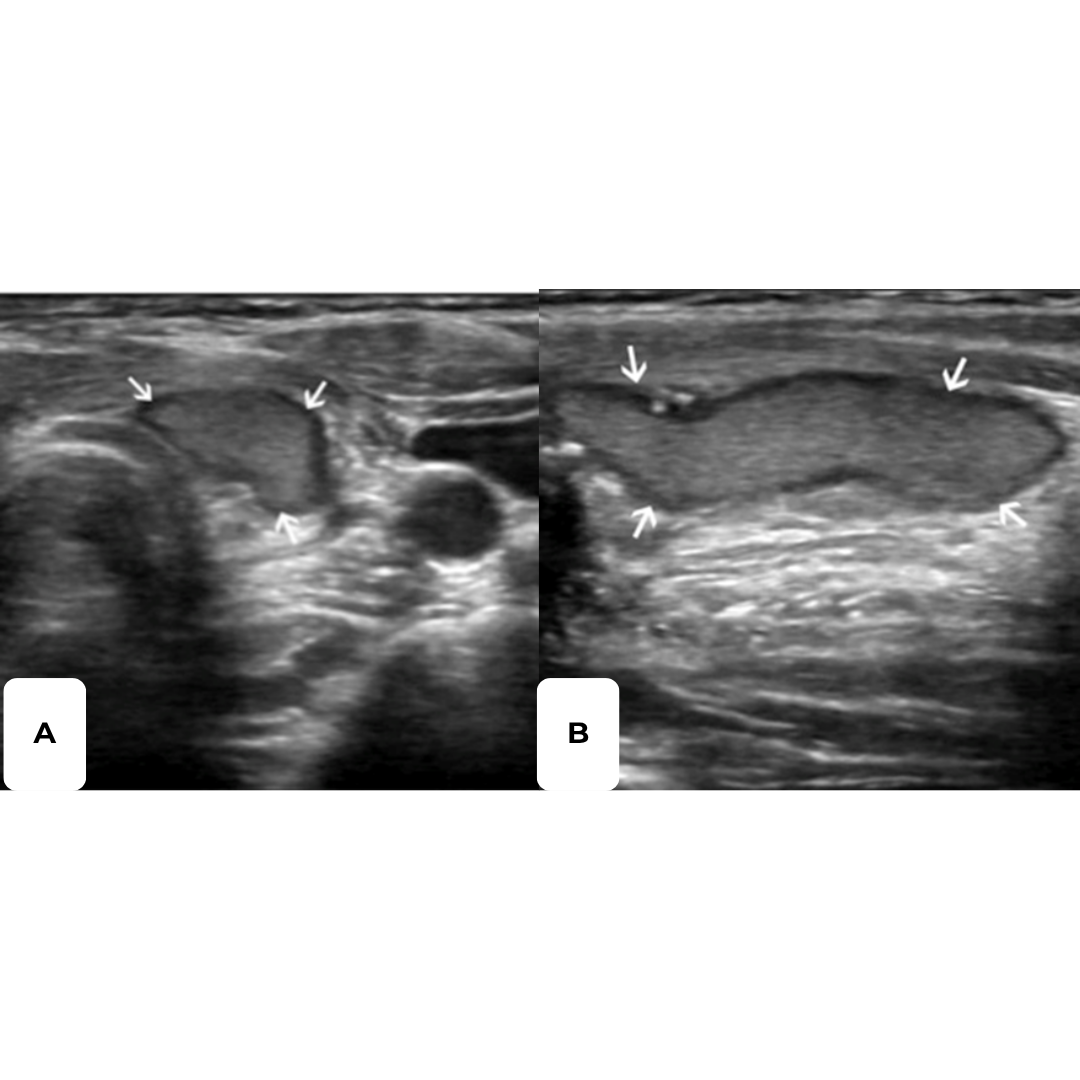

Figura 4. Hematoma post quirúrgico, por linfadenectomía izquierda, imagen (a) se observa corte longitudinal y en imagen (b) corte transversal a nivel del segmento cervical III.